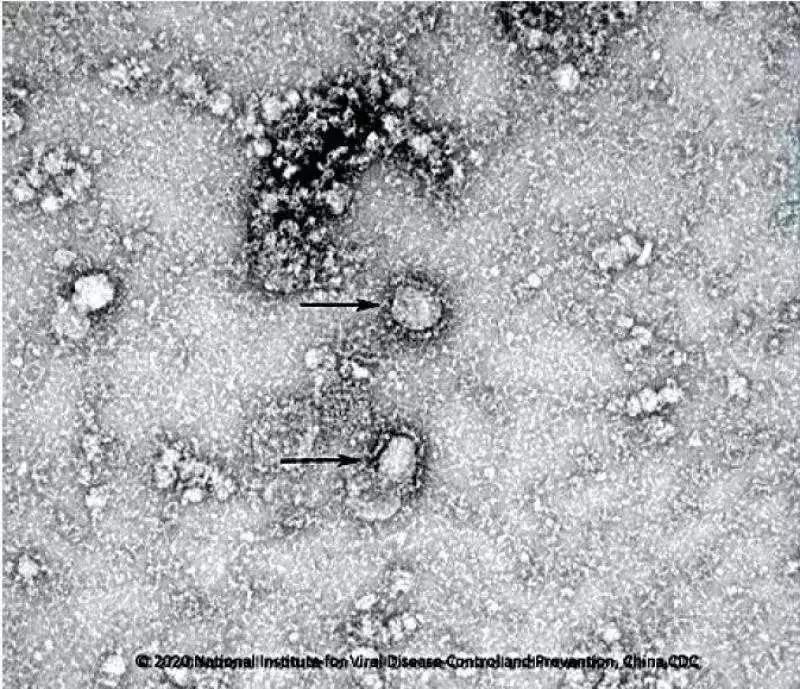

中國疾控中心開始研發新冠病毒疫苗,已成功分離病毒,正篩選種子毒株。

中國疾控中心已成功分離我國首株新型冠狀病毒毒種